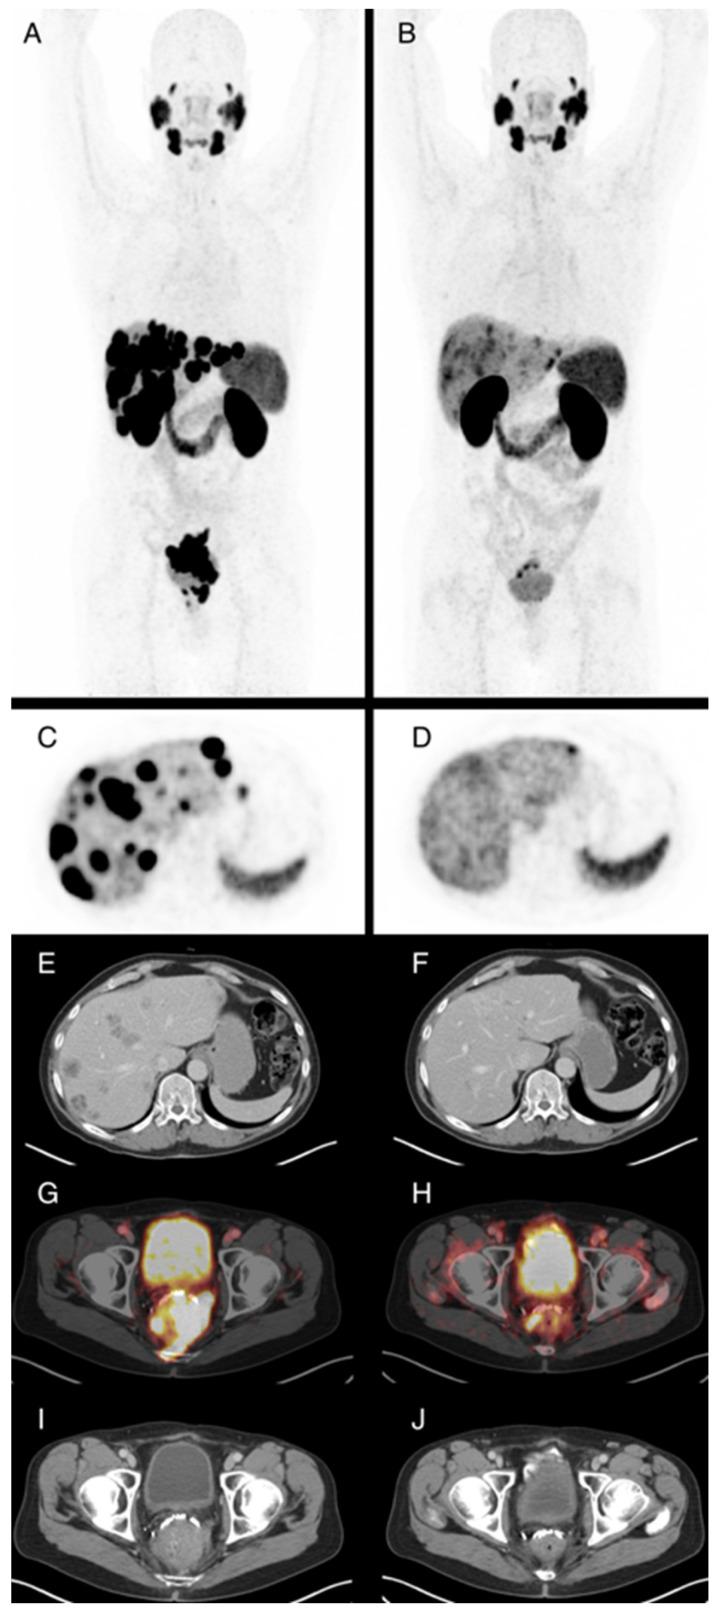

Castration resistant prostate cancer (CRPC) is characterized by an aggressive biological behavior with a relatively short survival time, especially in progressive tumors pretreated with new hormonal agents and taxane chemotherapy. [177Lu]-Lutetium-PSMA (Lu-PSMA) treatment has proven efficacy in these patients. However, around 30% of the CRPC patients do not benefit from Lu-PSMA treatment, and little is known about predictive factors for treatment success if Lu-PSMA is offered in an individualized approach based on clinical and laboratory features. In this monocentric retrospective study, 86 CRPC patients receiving Lu-PSMA treatment were evaluated. The focus of the study was to describe clinical factors at baseline and during early treatment that are related to overall survival (OS). In addition, PSMA PET/CT-, PSA-response, and safety and tolerability (CTCAE adverse event reporting) were assessed. Efficacy endpoints were calculated using stratified Kaplan-Meier methods and Cox regression models. Mean applied dose was 17.7 GBq (mean 5.3 ± 1.1 GBq per cycle) with an average of 3.6 (range 1-8) therapy cycles. Patients were followed up for a mean of 12.4 months (range 1-39). The median OS was 15 months (95% CI 12.8-17.2). The best overall response rate in patients assessed with PSMA PET/CT and PSA response was 27.9%, and 50.0% had at least stable disease. Nine patients had a ≥grade 3 adverse event with anemia being the most frequent adverse event. Positive predictors for prolonged OS from baseline parameters were pre-treatment hemoglobin level of ≥10 g/dL and a lower PSA values at treatment start, while the presence of visceral or liver metastases were not significantly associated with worse prognoses in this cohort. With careful patient selection, an individualized Lu-PSMA treatment approach is feasible and patients with dose-limiting factors or visceral metastases should be included in prospective trials.

去势抵抗性前列腺癌(CRPC)的特征是具有侵袭性生物学行为,生存时间相对较短,尤其是在用新型激素药物和紫杉烷化疗预处理的进展性肿瘤中。[177Lu] - 镥 - PSMA(Lu - PSMA)治疗已在这些患者中证明有效。然而,约30%的CRPC患者未从Lu - PSMA治疗中获益,对于基于临床和实验室特征以个体化方式提供Lu - PSMA治疗时治疗成功的预测因素知之甚少。在这项单中心回顾性研究中,对86例接受Lu - PSMA治疗的CRPC患者进行了评估。该研究的重点是描述基线和早期治疗期间与总生存期(OS)相关的临床因素。此外,还评估了PSMA PET/CT、PSA反应以及安全性和耐受性(CTCAE不良事件报告)。使用分层Kaplan - Meier方法和Cox回归模型计算疗效终点。平均应用剂量为17.7 GBq(平均每周期5.3±1.1 GBq),平均治疗周期为3.6个(范围1 - 8个)。患者平均随访12.4个月(范围1 - 39个月)。中位OS为15个月(95%CI 12.8 - 17.2)。通过PSMA PET/CT和PSA反应评估的患者中最佳总体反应率为27.9%,50.0%的患者至少病情稳定。9例患者发生≥3级不良事件,贫血是最常见的不良事件。基线参数中OS延长的阳性预测因素是治疗前血红蛋白水平≥10 g/dL以及治疗开始时较低的PSA值,而在该队列中内脏或肝转移的存在与较差预后无显著相关性。通过仔细选择患者,个体化的Lu - PSMA治疗方法是可行的,有剂量限制因素或内脏转移的患者应纳入前瞻性试验。